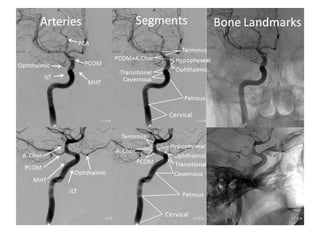

NORMAL MRA

Arteries of the brain (cranial view) - MRA

1. Anterior cerebral artery

2. Anterior communicating artery

3. Basilar artery

4. branches (in insula) of middle

cerebral artery

5. Cavernous portion of internal carotid

artery

6. Cervical portion of internal carotid

7. Genu of middle cerebral artery

8. Intracranial (supraclinoid) internal

carotid artery

9. Middle cerebral artery

10. Ophthalmic artery

11. Petrous portion of internal carotid

12. Posterior cerebral artery

13. Posterior cerebral artery in ambient

cistern

14. posterior cerebral artery in

interpeduncular cistern

15. Posterior communicating artery

16. Posterior inf cerebellar artery.

17. Quadrigeminal portion of posterior

18. Superior cerebellar artery

19. Vertebral artery

Arteries of the brain (lateral view) - MRA

4. branches (in insula) of middle cerebral artery

5. Cavernous portion of internal carotid artery

6. Cervical portion of internal carotid artery

8. Intracranial (supraclinoid) internal carotid artery

11. Petrous portion of internal carotid artery

13. Posterior cerebral artery in ambient cistern

14. posterior cerebral artery in interpeduncular

17. Quadrigeminal portion of posterior cerebral